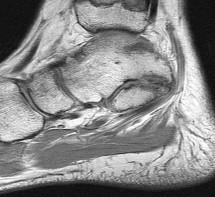

Figures 1a through 1c

Tarsal coalitions occur when primitive mesenchymal cells fail to differentiate and form the

normal articular separations between the tarsal bones of the hindfoot. Overall incidence is difficult to determine because many affected people are minimally symptomatic or asymptomatic. Symptomatic tarsal coalitions typically present in adolescents as a painful flatfoot; however, there are a number of possible presentations, and occasionally symptoms do not appear until adulthood. Most tarsal coalitions are between the calcaneus and the navicular (CN) and the talus and the calcaneus (TC). Although most TC coalitions are across the middle facet, posterior facet coalitions do occur. Plain radiographic evaluation of suspected tarsal coalition is the mainstay for diagnosis. However, coalitions can be bony or fibrous, and making the diagnosis can be difficult. The addition of CT images to distinguish bony definition and MR images to decipher soft tissue can aid in diagnostics. Bony coalitions appear as definite bony bridging between the bones, while fibrous coalitions are suspected when distortion of the bony anatomy is seen. Bony coalitions are best seen on the oblique view (CN) and Harris axial view (TC). There are a number of secondary signs such as the anteater (AE) sign (elongation of the anterior process of the calcaneus as it extends to the navicular as seen on the lateral view [CN]). talar beaking (traction spur of the talar neck thought to result from abnormal stresses as seen on the lateral view [both CN and TN]), and the “C” sign (a continuous cortical contour from the medial talus to the sustentaculum tali [ST]) as seen on the lateral view (TC). A number of newer signs are not as well known, such as a broad mediolateral dimension of the navicular on the anteroposterior (AP) view (the

navicular is wider than the talar head [CN]), nonvisualization of the middle facet on the lateral view (TC), the brick sign (a normal ST is flat, but a distorted ST is enlarged and curved [CN]), and a tapered lateral navicular bone as seen on the AP view (the medial navicular [CN] is much thicker than the lateral navicular).

Figure 1a shows talar beaking (TB), an AE, and an open middle facet (MF). Figure 1b shows a wide navicular (WN), and Figure 1c shows an abnormal articulation between the calcaneus and the navicular, all consistent with a CN coalition.